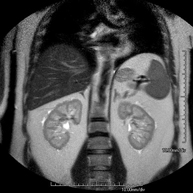

Prova diagnòstica no invasiva que consisteix en l'obtenció d'imatges d'alta definició anatòmica del fetge mitjançant l'ús d'un camp electromagnètic i ones de ràdio (amb un emissor i un receptor). No utilitza radiació ionitzant. Es realitza per estudiar qualsevol lesió localitzada en el fetge. Normalment es requereix l'ús de contrast paramagnètic (Gadolini) per caracteritzar les lesions. És necessari realitzat la prova en dejú (6 hores). - RM de Ronyons

Prova diagnòstica no invasiva que consisteix en l'obtenció d'imatges d'alta definició anatòmica d'ambdós ronyons mitjançant l'ús d'un camp electromagnètic i ones de ràdio (amb un emissor i un receptor). No utilitza radiació ionitzant. Es realitza per estudiar qualsevol lesió localitzada en ambdós ronyons. Normalment es requereix l'ús de contrast paramagnètic (Gadolini) per caracteritzar les lesions. - RM de Glàndules Suprarenals

Prova diagnòstica no invasiva que consisteix en l'estudi de les artèries renals per obtenir imatges d'alta definició anatòmica mitjançant l'ús d'un camp electromagnètic i ones de ràdio (amb un emissor i un receptor). És indispensable l'ús de contrast paramagnètic (Gadolini). No obstant, no utilitza radiació ionitzant. La qualitat de les imatges permet realitzar reconstruccions en 2D i 3D. Aquesta prova està indicada en aquells pacients que pateixen d'HTA refractària al tractament, en pacients amb lesions renals per tenir un mapa "vascular" pre-quirúrgic, etc. - Sencer-RM